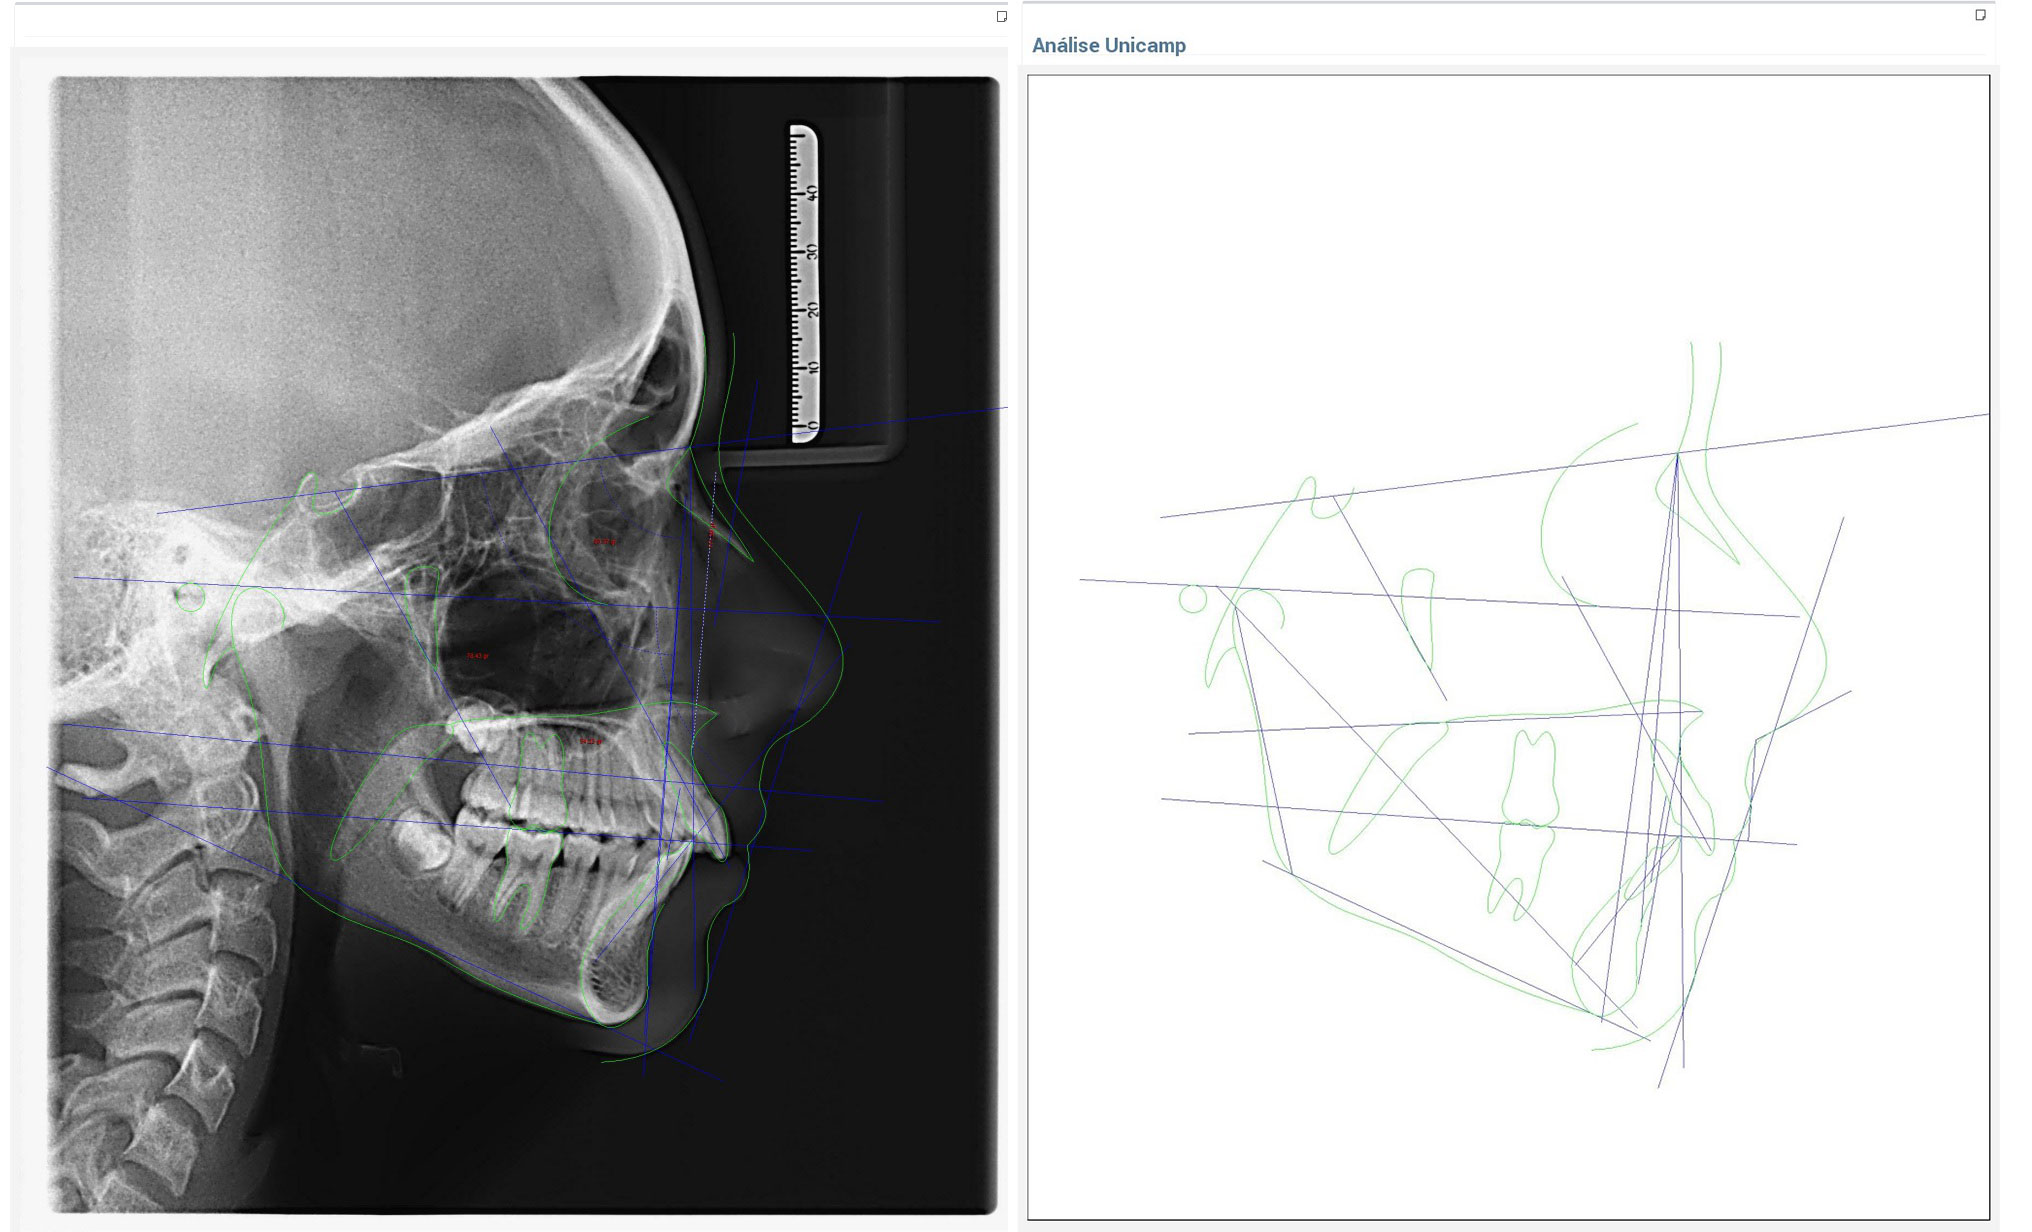

Radiografias Digitais

- - Raio X Panorâmico

- - Telerradiografias

Documentações Ortodônticas

- - Radiografias digitais com laudos e análises